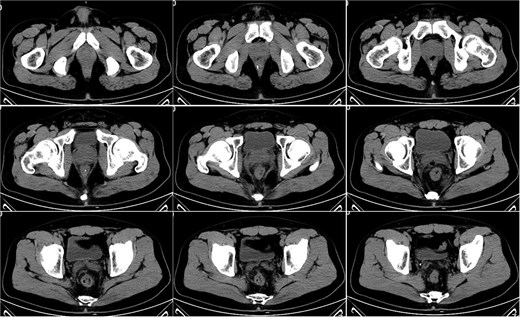

On postoperative Day 10, a repeat complete blood count showed a white blood cell count of 9.74 × 109/l and a neutrophil percentage of 69.5%. The patient’s temperature ranged between 36.4 and 37.4°C, and abdominal discomfort was partially alleviated. A follow-up pelvic CT scan revealed a breach in the anterior rectal wall with gas density shadows communicating with the surrounding area, accompanied by filamentous exudate density shadows and multiple gas density shadows (Fig. 2). These findings indicated rectal wall edema and anterior wall perforation with surrounding infection. Anorectal examination revealed a 0.5 × 0.5 cm ulcerative lesion at the 5 o’clock position of the anastomosis site in the knee–chest position. This was considered rectal perforation secondary to anastomotic dehiscence. Given the absence of peritoneal irritation signs and normalization of the white blood cell count, a conservative treatment plan was adopted after discussion with the patient. This plan involved continuing anti-infective treatment with intravenous cefoperazone sodium and sulbactam sodium.